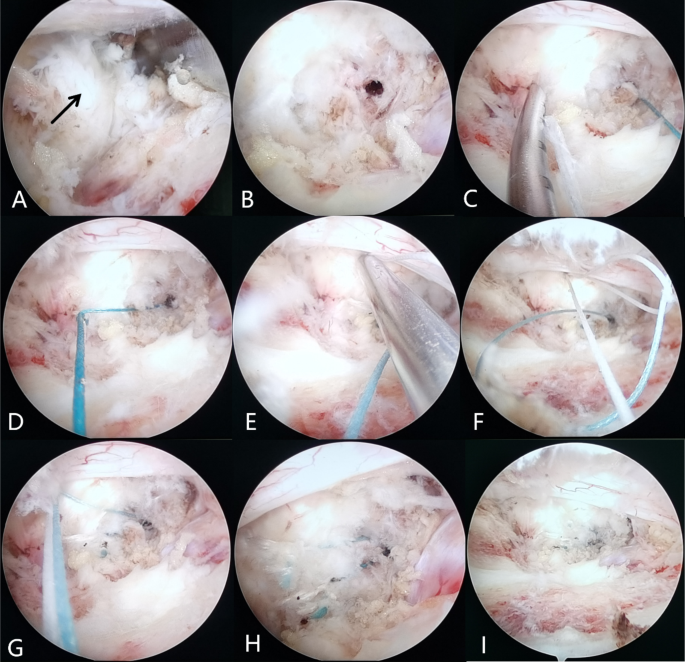

The surgical procedure of the triangular-shaped bone-anchoring annulus fibrosus suture technique under arthroscopic-assisted uni-portal spinal surgery. (A) Exposure of the protruding nucleus pulposus. (B) Excision of the nucleus pulposus reveals the damaged annulus fibrosus and a bone tunnel was drilled into the inferior vertebral body. (C,D) Penetration of the first stitch into the inferior vertebral body and tightening of the broken annulus fibrosus with the first stitch. (E) Penetration a second stitch on the broken fiber ring. (F,G) Tightening the knot with the previous suture from the previous bone tunnel. (H,I) Cutting the two stitches after knotting and no visible compression of the nerve root after suturing.